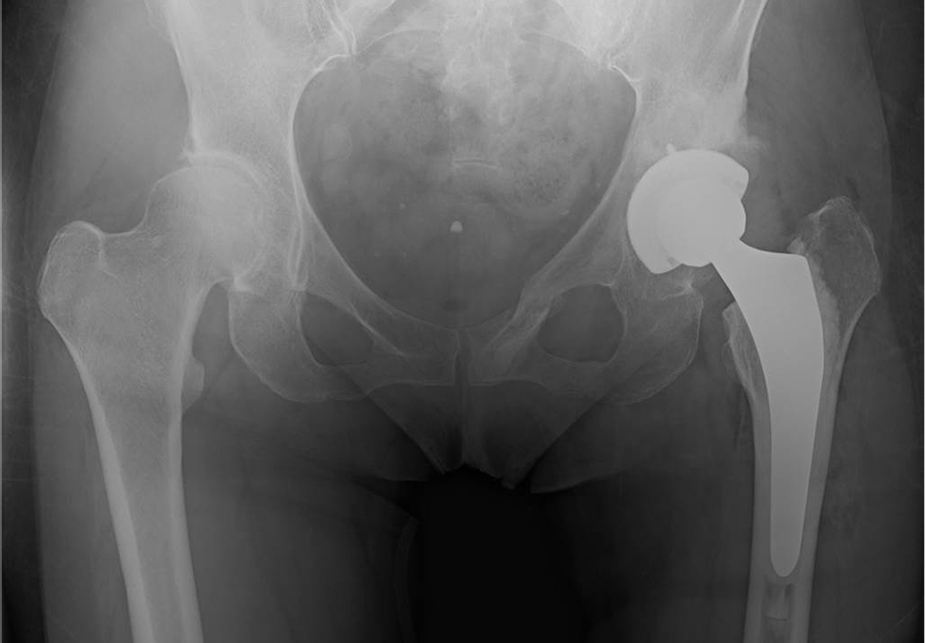

〈手術後のレントゲン〉(正面)

〈手術後のレントゲン〉(側面)

当院にて人工股関節全置換術(THA)を施行。アプローチはAMIS(前方最小侵襲手術)で行い、術後は強い痛みを訴えることもなく、術翌日より歩行器歩行を開始しスムーズにリハビリをすすめられました。